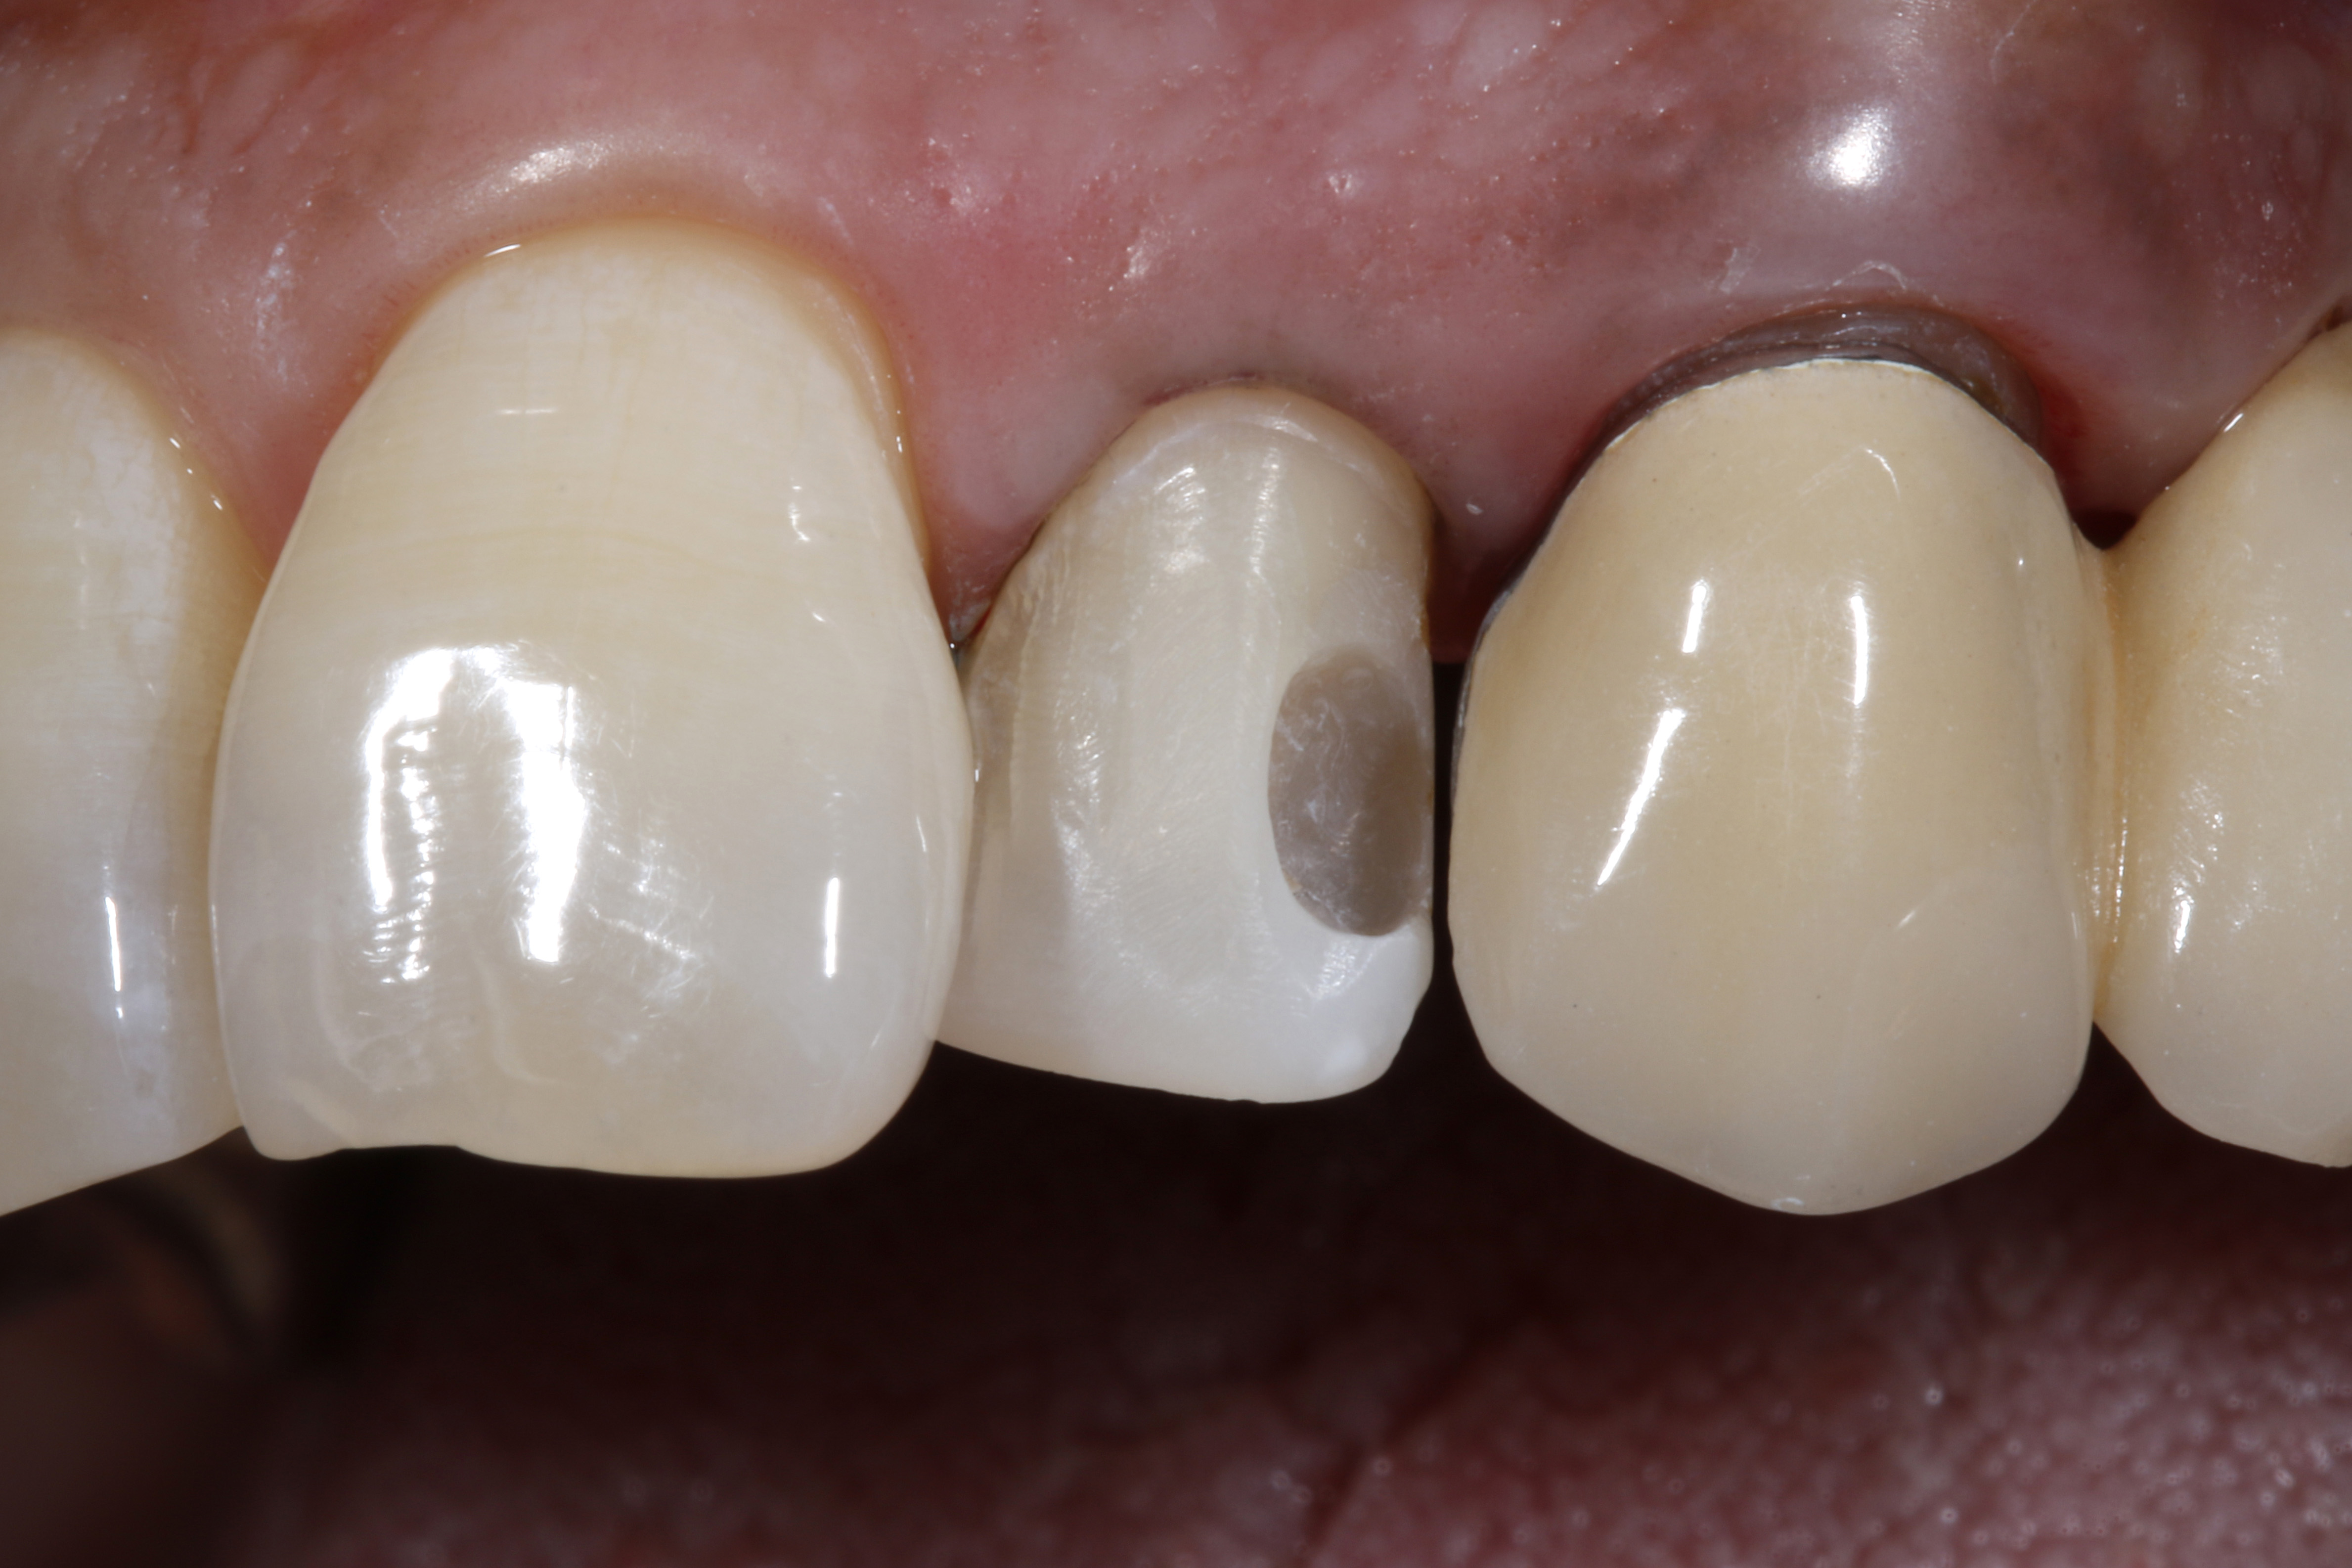

Ryc. 4. Usunięcie starego, dystalnego wypełnienia kompozytowego i niewielka preparacja powierzchni wargowej pod bezpośrednią licówkę kompozytową.

Ryc. 5. Odsunięcie dziąsła brzeżnego za pomocą nici retrakcyjnej w celu odsłonięcia brzegu preparacji od strony przyszyjkowej, co spowodowało krwawienie z bruzdy